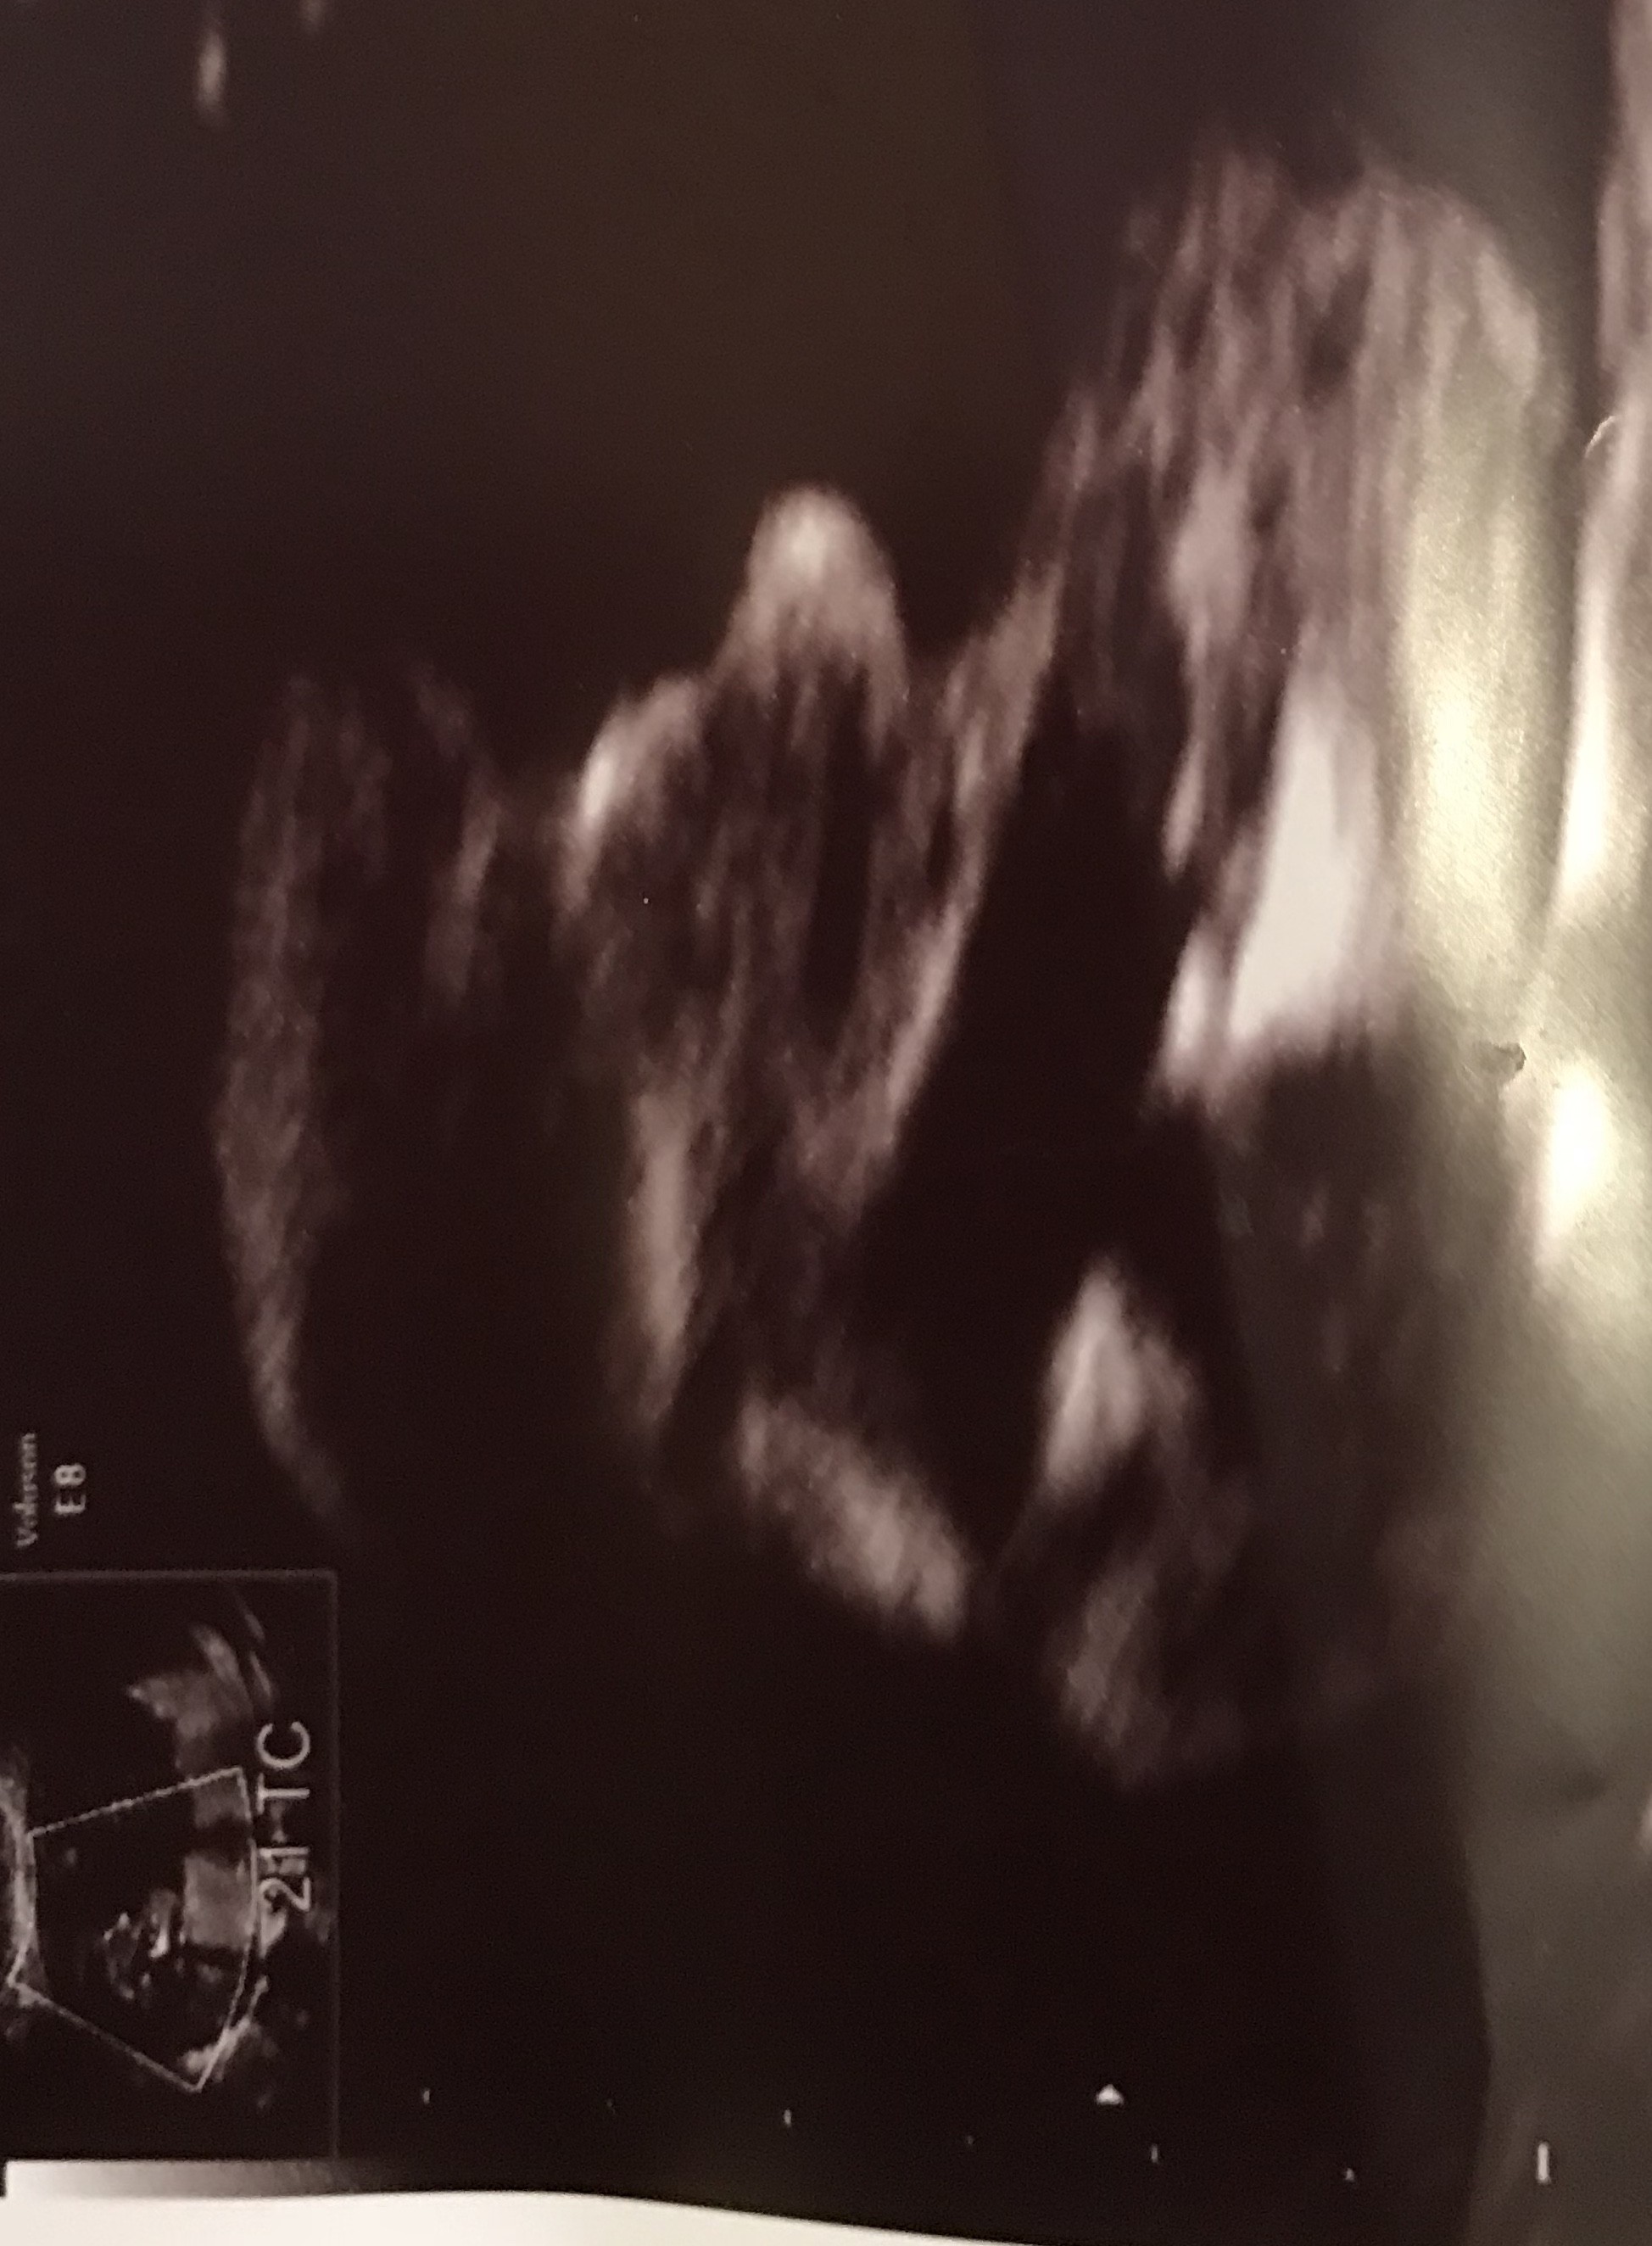

Cześć dziewczyny. Co sądzicie o moich zdjęciach? W 11tc5dc pierwsze zdj-lekarz stwierdził że na 75prc. dziewczynka. Tydzien później jeszcze raz byłam u niego, bo jeszcze musiał coś podejrzeć i w 12tc5d następne zdjęcia-powiedział że dziś na 75 prc. chłopak. Powiedział ogólnie że daje 50proc i trzeba poczekać do połówkowego. Czy ktoś miał tak szybką zmianę płci. Zdjęcia z obydwu badań wydają się jednoznaczne: na pierwszym dziewczynka, na drugim chłopiec. Czy już zostanie chłopiec?? Czy jest szansa że się zmieni? Ktoś tak miał? Dałybyście 100proc chłopak, czy jakąś nadzieję na dziewczynkę? Lekarz uznał, że jest jakiś procent kobiet u których się to zmienia, nie wiem co miał na myśli.

Za wczesnie lekarz ocenil plec pierwszym razem dlatego ze nub do 13 tc moze sie podniesc ...na poczatku wszystkie nuby sa dziewczynkowe.Raczej nastawialbym sie na chlopca ale poczekaj na polowkowe.